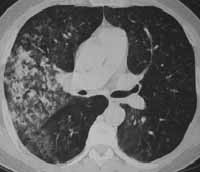

Figuras 6 y 7. Rx tóraxcon infiltrados en base de hemitórax derecho. TAC de tórax con infiltrados alveolares parahiliares derechos. La patología fue compatible con adenoma bronquioalveolar.